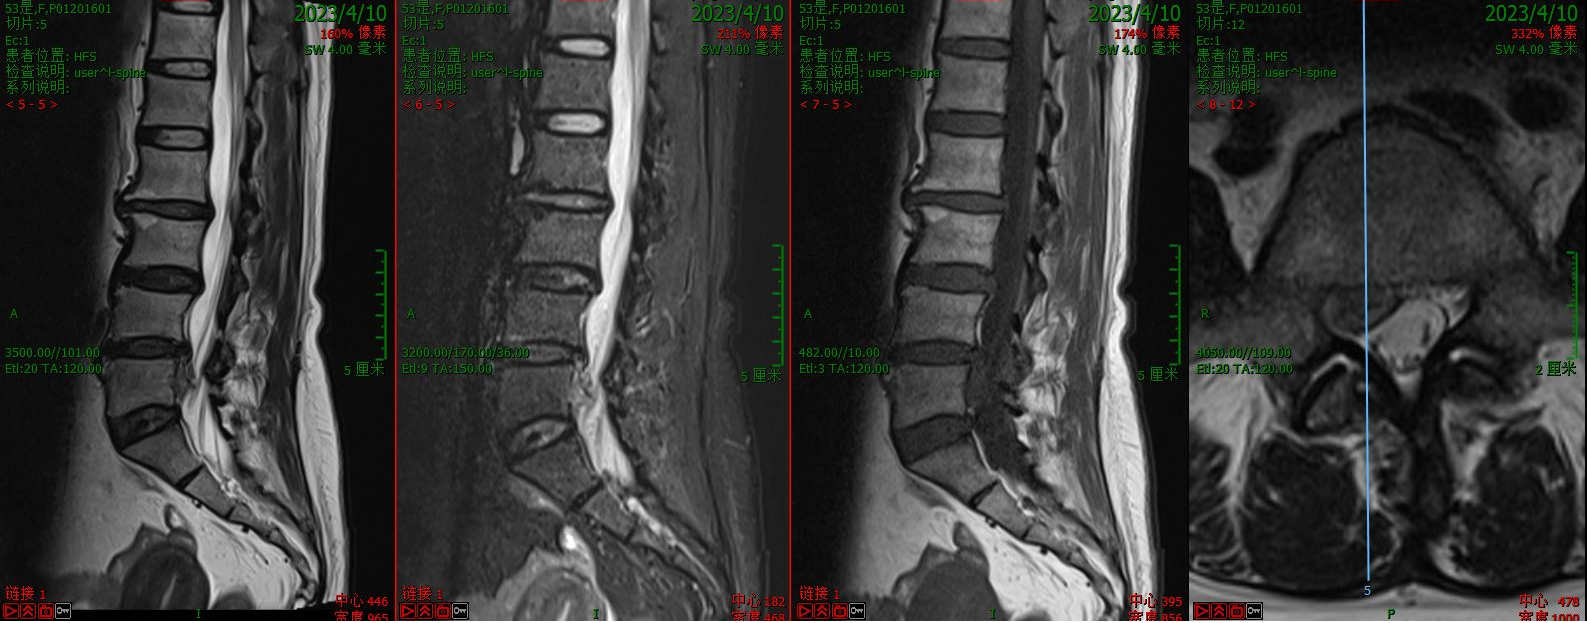

第一例病例为一名中年男性,腰4/5椎间盘突脱出并向下游离接近腰5/骶1椎间隙,为其实施VBE内镜下突出髓核单纯摘除术。患者术前腰痛伴右下肢疼痛麻木1个月余,右拇指背伸肌力明显下降。术后疼痛完全缓解,肌力较前部分恢复,有轻度麻木。

术前核磁